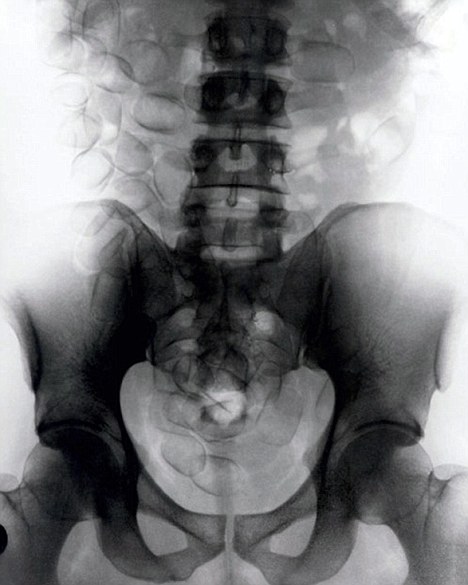

現(xiàn)年30歲的菲達(dá)利斯(Fidelis Ozouli)冒著生命危險(xiǎn)將重達(dá)1公斤的毒品吞下,被抓后卻辯稱不知道吞下的是毒品。當(dāng)時(shí),曼徹斯特機(jī)場(chǎng)的海關(guān)人員看到毒販菲達(dá)利斯臃腫的肚腩,顯得很不自然,于是開始懷疑。檢查人員用X射線機(jī)照他的胃部時(shí),發(fā)現(xiàn)了大量可卡因。目前他已被送往附近醫(yī)院,以確保排出所有的毒品。